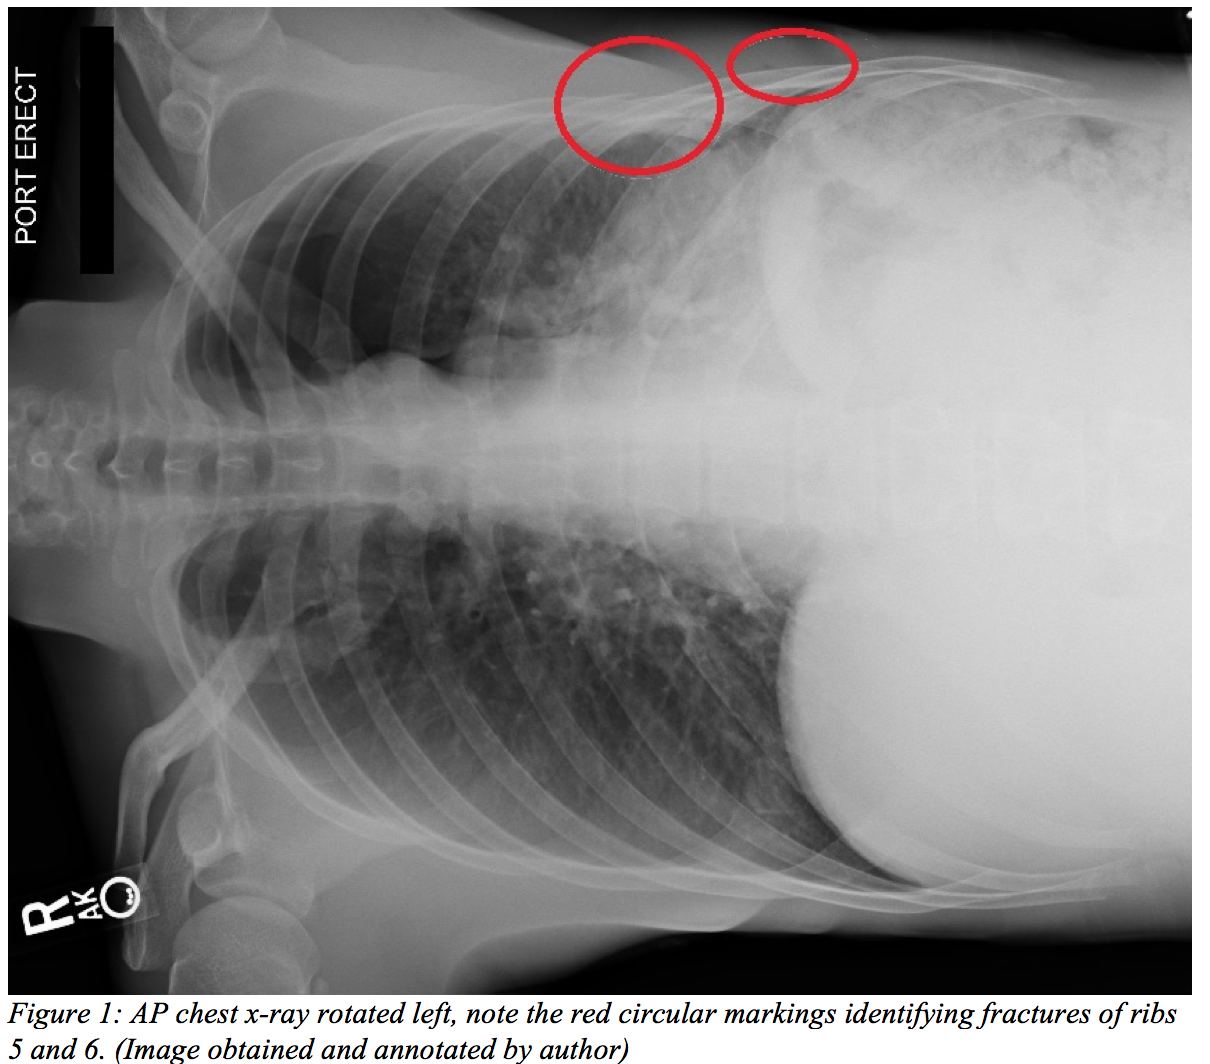

- If you’re having difficulty appreciating a lateral rib fracture on a chest x-ray (CXR), try rotating it 90° with the concerning side pointing upwards. Because this breaks up the usual chest radiograph pattern that your brain is accustomed to, your vision does a better job of “seeing” each rib as it is, rather than defaulting to a normal interpretation.

Following our exam, the patient was placed on 3 liters of oxygen via nasal cannula. His dyspnea continued, and his oxygen saturation only improved to 90% after 5 minutes. He was then switched to 10 liters of oxygen via non-rebreather. Given the shortness of breath and point tenderness over the left anterior and lateral chest wall, a chest x-ray was ordered and interpreted using some of the pearls above.

- 50/50 Rule (part 2): Within the first few days following an injury, 50% of rib fractures are not seen on a CXR.2